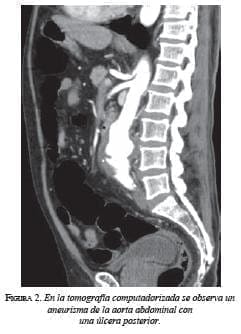

Durante su evolución, a pesar de la disminución de las deposiciones diarreicas, persistió el dolor abdominal. Se decidió solicitar una ecografía abdominal en la que se encontró una dilatación fusiforme de la aorta infrarrenal, con trombosis parcial y ulceración posterior de 14 mm. Ante estos hallazgos, se solicitó una angiotomografía que confirmó la dilatación fusiforme de la aorta abdominal infrarrenal de la arteria renal izquierda (figura 1), originada 13 mm en sentido caudal, con una longitud de 84 mm y un diámetro transverso máximo de 48 mm, con un hematoma intramural lateral izquierdo que comprometía la luz del vaso en el 40% (figura 2).